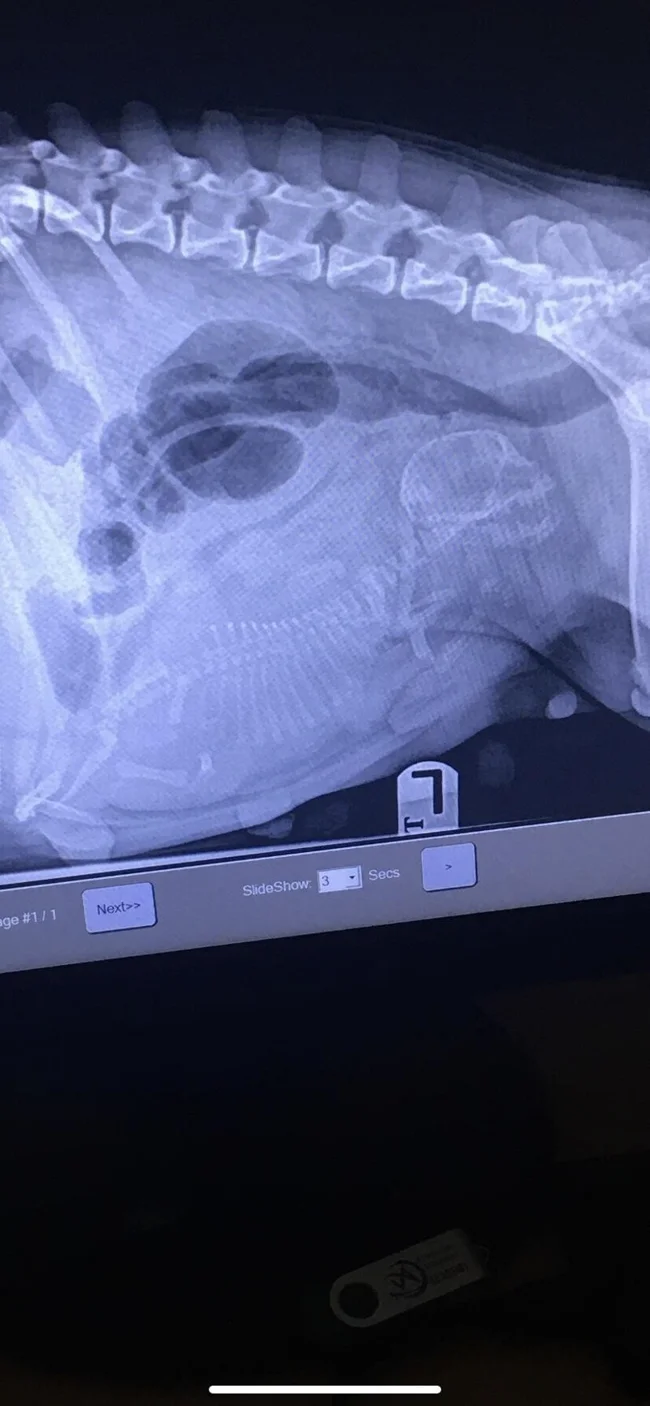

Рентген вагітної собаки